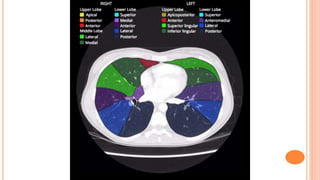

Mostly this means as the lung parenchyma.

Lung fields can be divided into zones: upper, middle,

and lower zones (Figure-12);

•Upper zone: from the apex to 2nd costal cartilage.

•Middle zone: between 2nd and 4th costal cartilage.

•Lower zone: between 4th and 6th costal cartilage

E – EXTRATHORACICTISSUES Mostly this means as the lung parenchyma. Lung fields can be divided into zones: upper, middle, and lower zones (Figure-12); •Upper zone: from the apex to 2nd costal cartilage. •Middle zone: between 2nd and 4th costal cartilage. •Lower zone: between 4th and 6th costal cartilage